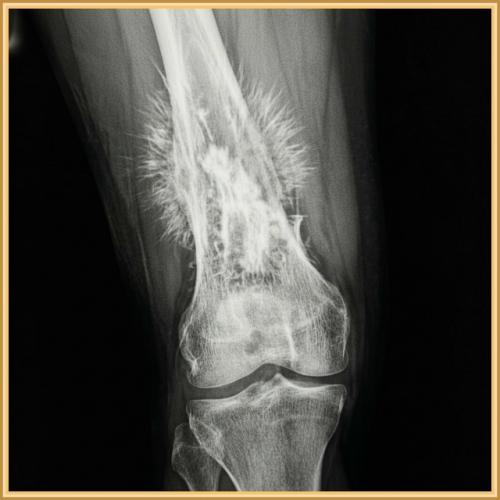

Перед вами кость, пораженная остеосаркомой. Самый жуткий и одновременно информативный признак здесь - так называемые спикулы, или игольчатый периостоз. Видите эти острые, торчащие "Лучи", словно ежиные иглы? Они не случайны. Это не просто деталь, это ярчайший индикатор агрессивного роста опухоли, которая с невероятной скоростью вторгается в окружающие ткани, формируя новые, хаотичные костные структуры.

Для онкологов и рентгенологов подобная картина на снимке - это не просто диагноз, это тревожный сигнал, требующий немедленных действий. Игольчатый периостоз часто указывает на высокую степень злокачественности опухоли и ее стремительное развитие. Каждый день промедления в таких случаях может стать критичным. Это гонка со временем, где на кону - жизнь пациента.